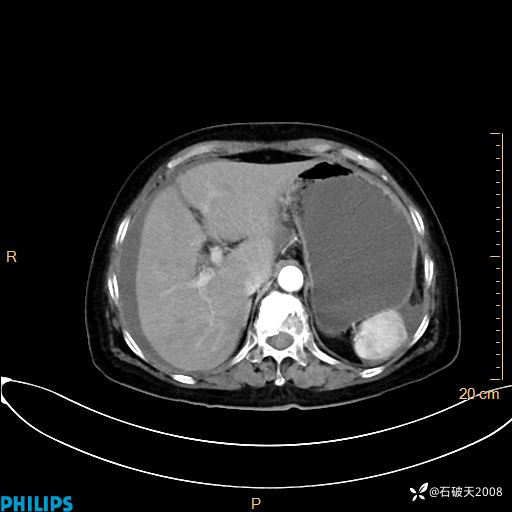

MIP